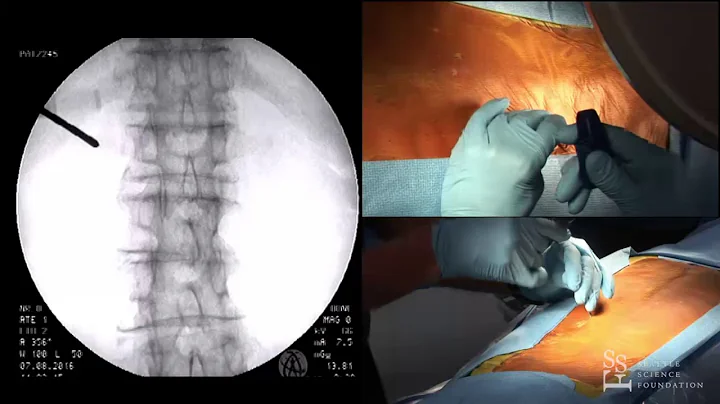

Vertebral Augmentation: Why It’s A Game-changer For Patients | Drs. Anthony Giuffrida & Doug Beall

Join Dr. Anthony Giuffrida and Dr. Douglas Beall in this Global Spine Initiative podcast episode as they dive into vertebral ...